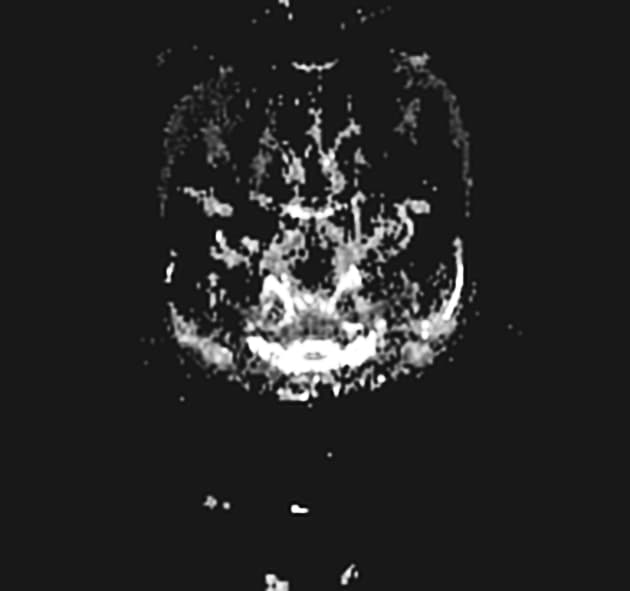

Chụp MRI theo dõi sau 15 ngày ngừng thuốc...

Chụp MRI theo dõi sau 15 ngày ngừng thuốc 5-FU cho thấy gần như giải quyết hoàn toàn các vùng hạn chế khuếch tán, chỉ còn khuếch tán hỗ trợ tối thiểu tại phần bản lề của thể chai và vùng trung tâm bán nguyệt hai bên. Kết quả này tương ứng với việc giải quyết hoàn toàn các triệu chứng thần kinh của bệnh nhân.

Hình ảnh khuếch tán (DWI) đóng vai trò quan trọng cả trong giai đoạn cấp tính và theo dõi, để chứng minh tính hồi phục sau điều trị.

- "Các triệu chứng thần kinh và tổn thương hình ảnh thường hồi phục sau khi ngưng 5-FU."

- "Các dãy hình ảnh DWI và ADC rất quan trọng để phát hiện sớm và theo dõi bệnh não chất trắng độc hồi phục."